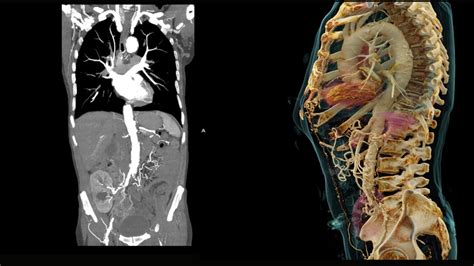

Preventative Diagnostic Center on a scan that can save lives KLAS

Fillable Online Preventative Diagnostic CenterLowDose CT Scans Las